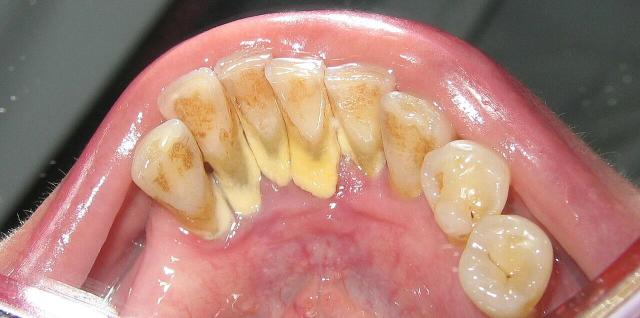

牙齿上的牙结石(牙根处黄色部分) 图源:wikipedia